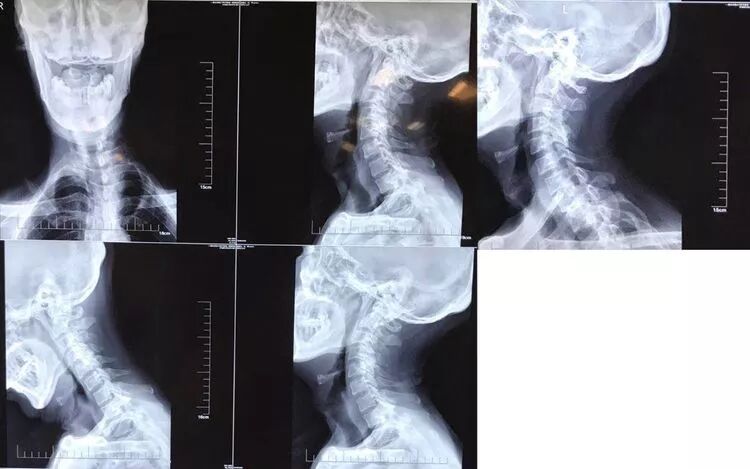

影像学资料

1. Chiairi畸形并颈髓空洞

2. 脊柱侧弯